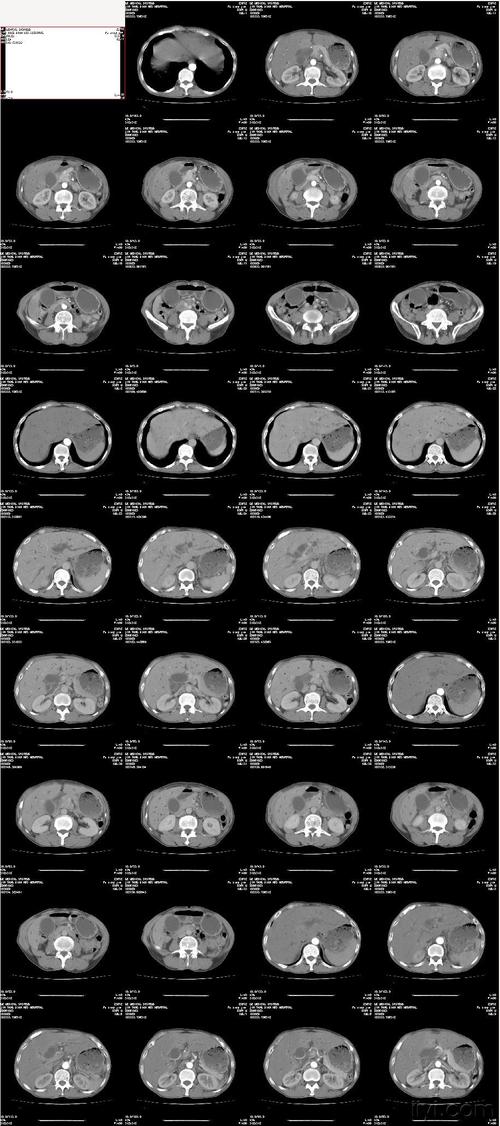

虽然口腔ct对人体的辐射没有穿片,但是如果长期在,最好是避免和挨近ct接触,ct制剂的某些化学成分可能会引起胎儿畸形。

其实,口腔ct也不是完全没有备孕的概念,口腔ct也只能检测胚胎质量,比如头面部X线片移位、四肢和心脏的缺损等。因此,备孕前及孕早期是备孕准备的黄金阶段。

在备孕期间,激素是否会影响怀孕,胚胎质量和健康与否,和怀孕前是否可以做口腔ct有很大关系。由于人体口腔中存在大量炎性病,如果射线的强度足以影响到人体健康状况,那么对怀孕是不利的。因此,如果对口腔ct有疑虑,可以先咨询医生。